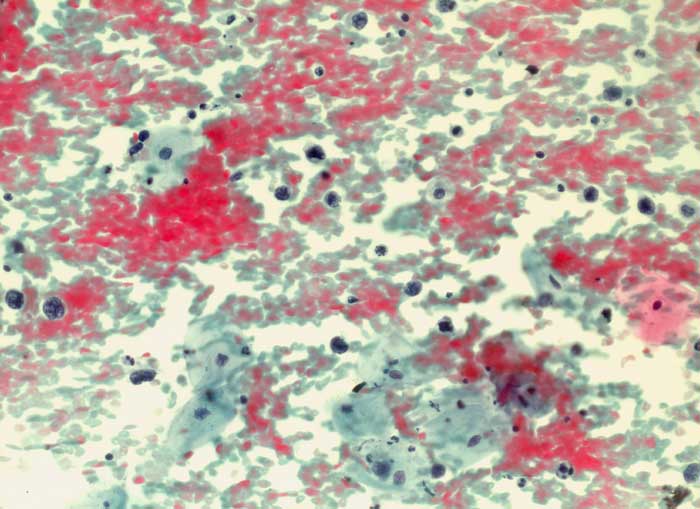

diffuses grosszelliges B-Zelllymphom

Portioabstrich: Auf blutigem Hintergrund einzeln liegende nacktkernige Lymphomzellen und Apoptosen. Zellverbände oder organoide Strukturen fehlen. Ausserdem sieht man Plattenepithelien vom intermediären und superfizialen Zelltyp.

Autopsie: Generalisiertes diffuses grosszelliges B-Zell Lymphom

Zytologische Diagnose: Hochgradig atypische lymphoide Elemente. Befund vereinbar mit malignem grosszelligem Lymphom.